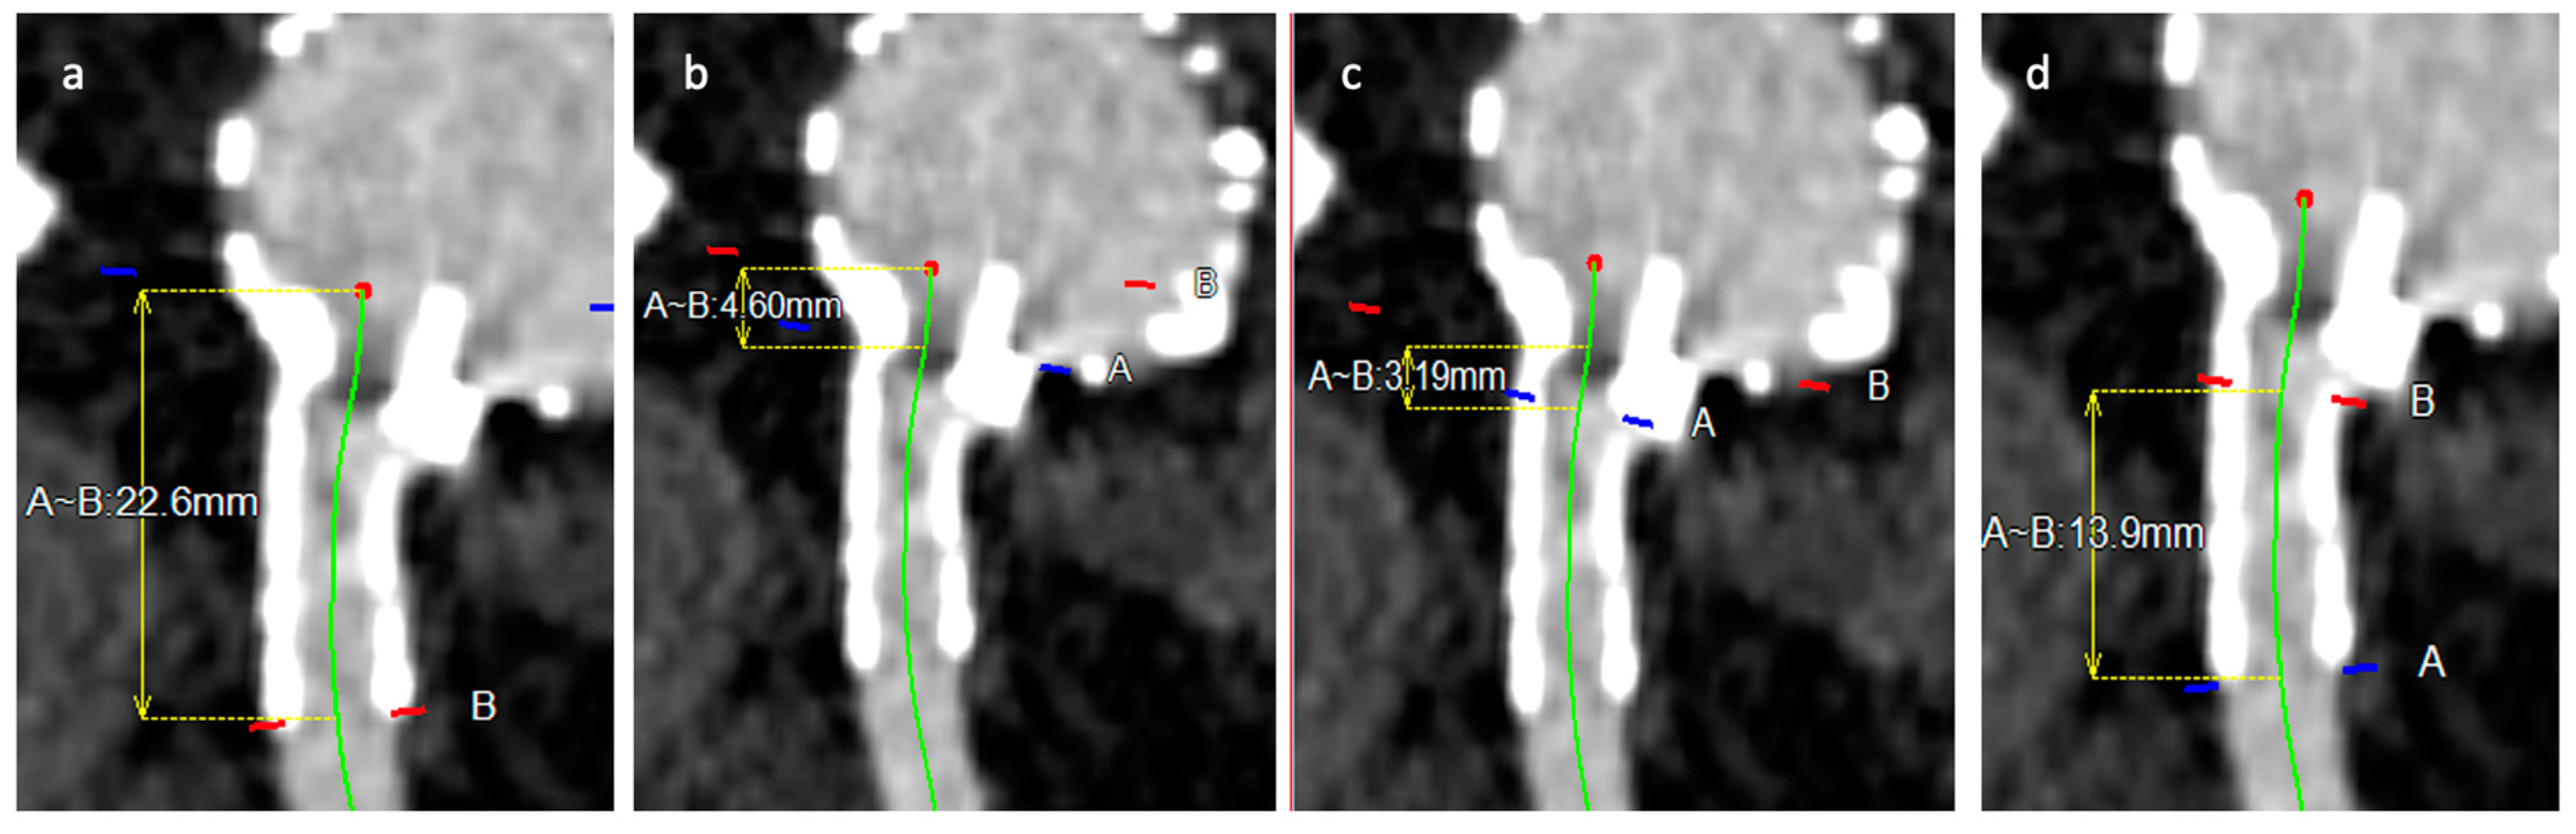

- Tortuosity index: calculated as a ratio between length of bridging stent along the centerline and the linear distance between beginning and end of bridging stent (Figure 2).

- Total bridging stent length: length of stent between the beginning of the branch until the end of stent in target vessel (Figure 3).

- Bridging stent sealing length: length of the stent apposition to the arterial wall into the target vessel (Figure 3).

- Bridging length (gap): length between the end of main body branch and the origin of the target vessel (Figure 3).

- Protrusion: length of bridging stent protrusion from fenestration into aortic lumen (Figure 3).